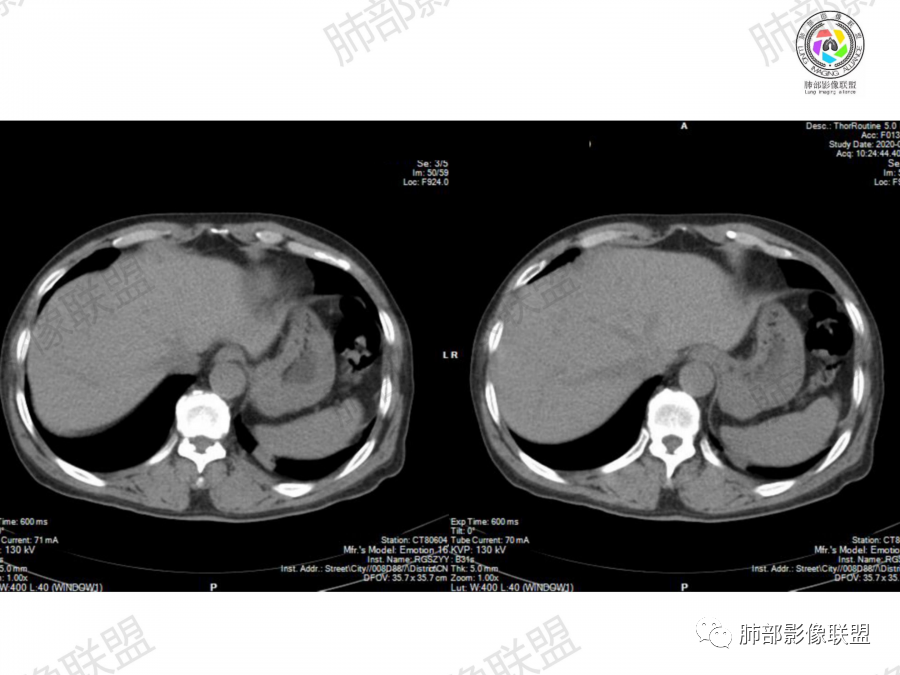

1、老年男性,大量吸烟史,无症状,体检左下肺孤立结节。

2、影像表现:无肺气肿背景、定位左肺下叶后基底段,不规则结节、与支气管关系不明确,部分边缘平直、部分膨隆,病变与胸膜宽基底相连,病变与胸膜糊墙征,病变周围见细、长、软毛刺,病变密度比较均匀。影像总体倾向炎症、符合肺组织慢性炎症伴机化。

综合分析:

该例病变虽然为老年男性,无肺气肿背景,无临床症状、长软毛刺、刀切边缘、糊墙,病灶密度均匀,周围支气管无截断,病灶密度均匀,基本为良性炎性病变特征,但并不是绝对,工作中应该建议治疗后随访排外其它。